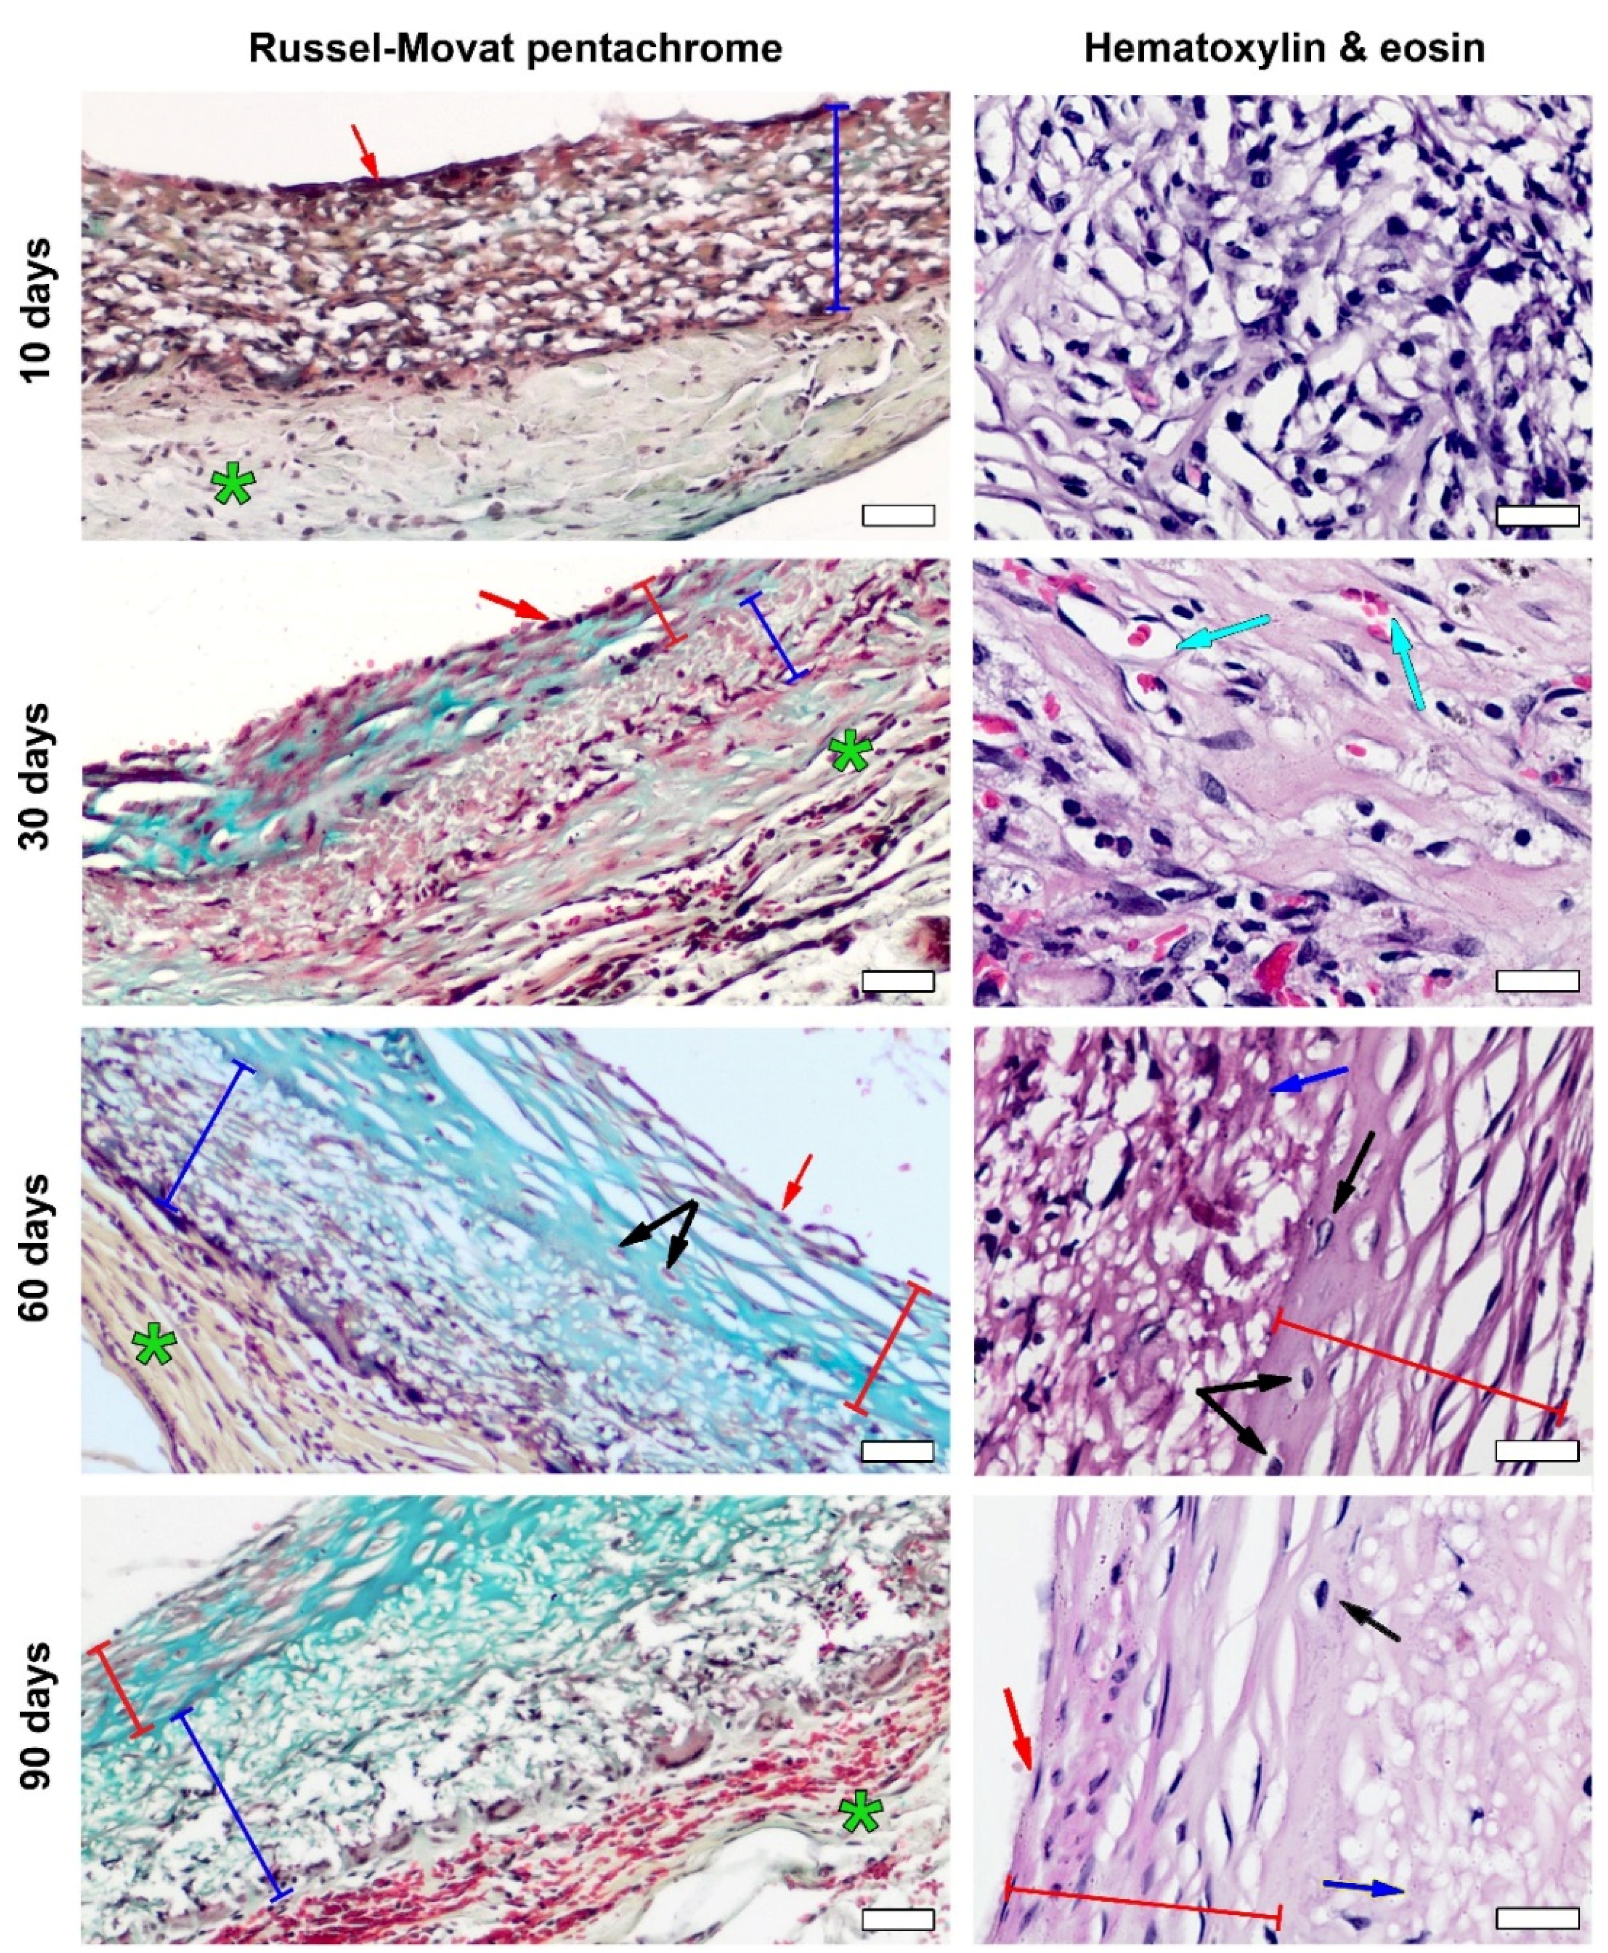

2.9. Histology

3.3. PCL Graft Transformation in Dynamics

4. Discussion